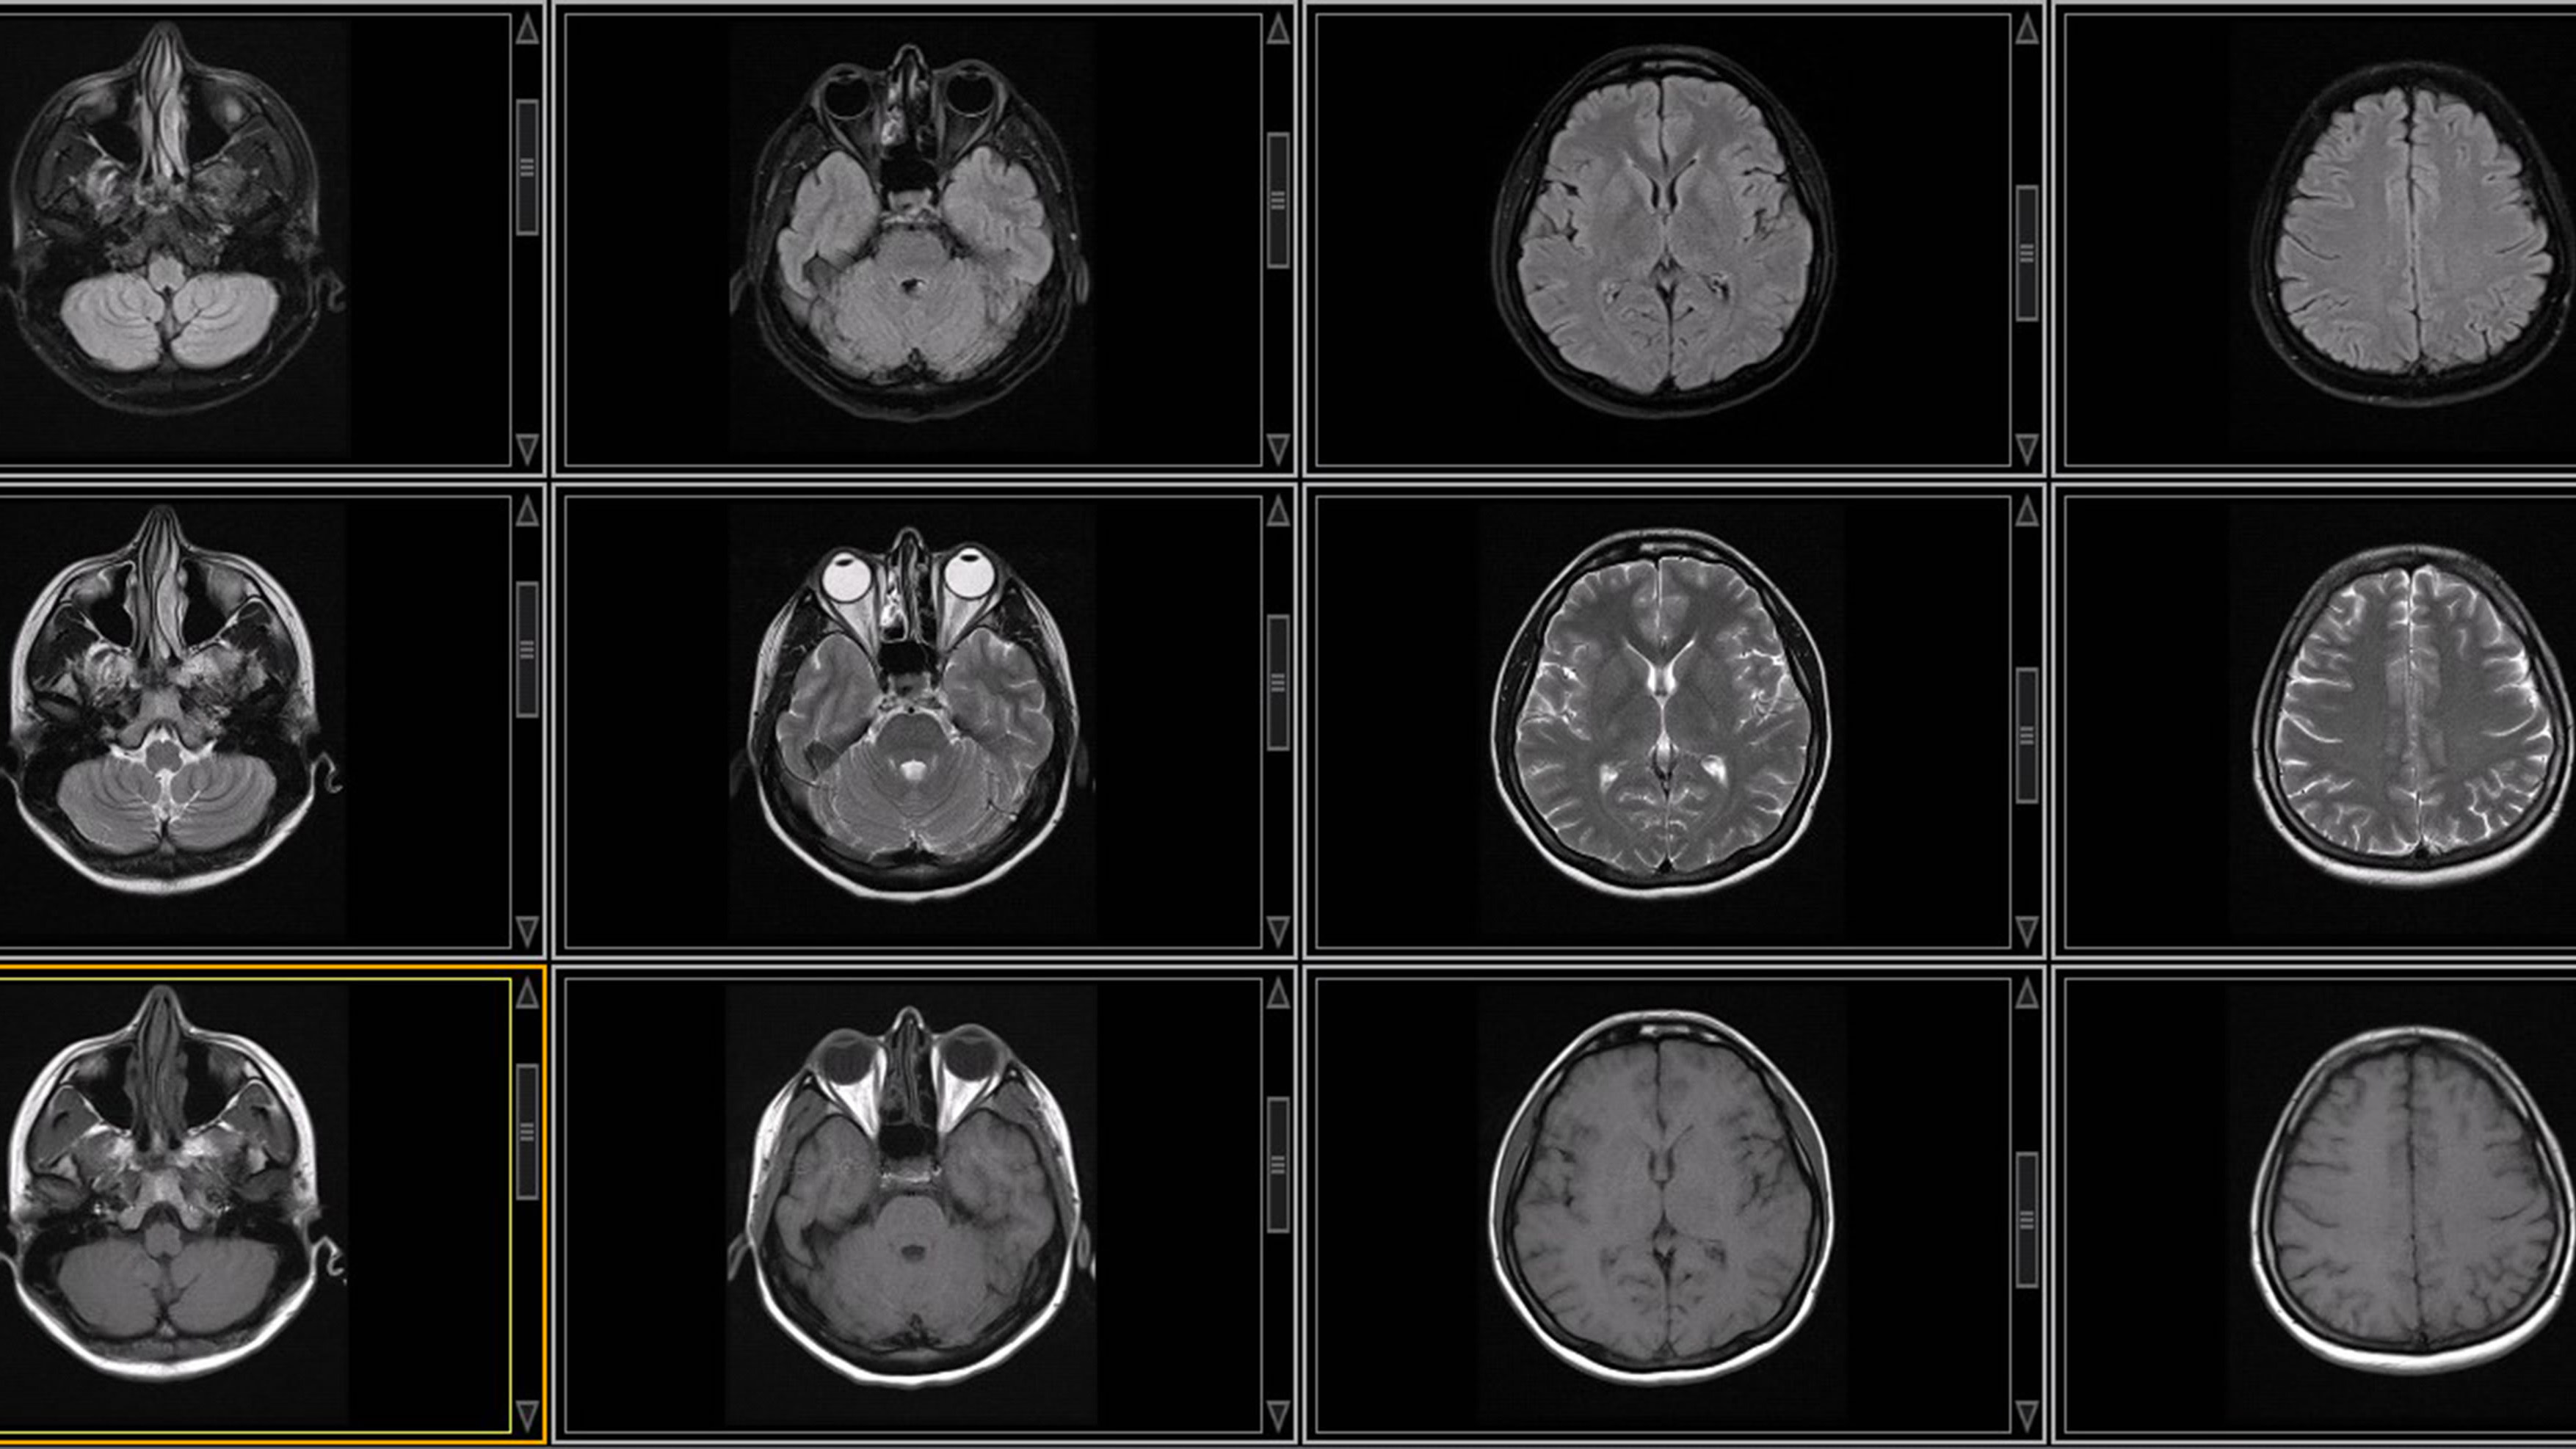

UTHealth Houston's Neurosurgery and Neural Interfaces Group advances neuromodulation, imaging, and brain-computer interfaces for treating brain disorders.